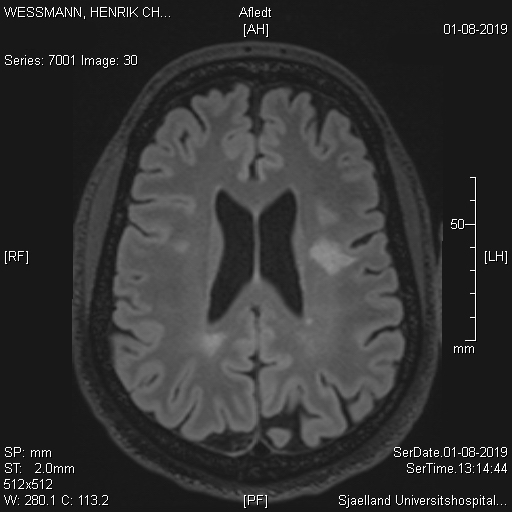

Det var både sjovt og ikke sjovt at se MR scanningsbillederne. Billedet i toppen, som viser min hjerne set fra isse med meget udstående øjne er sjovt.

Mindre sjovt er disse billede:

Det viser nogle store hvide pletter i hjernen. Det er plaque fra MS attakker og grunden til at jeg idag er invalidepensionist.